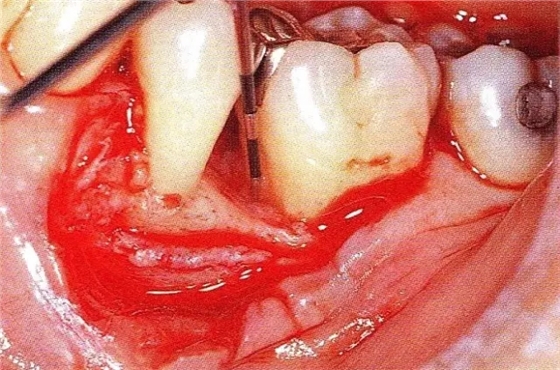

▲圖7-1左下6近中可觀察到3壁性垂直性骨缺損。此病例考慮到齦瓣供血關(guān)系,在前磨牙部位進(jìn)行了減張切開,沒有進(jìn)行縱切開。并利用刮治器、牙周外科用車針進(jìn)行了徹底的骨缺損部位搔刮。

▲圖7-3將posterior interproximal類型的非吸收性覆膜修整后進(jìn)行垂直懸吊縫合做固定。垂直懸吊縫合后,確定覆膜是否會(huì)動(dòng)搖,再將齦瓣與之緊密縫合。